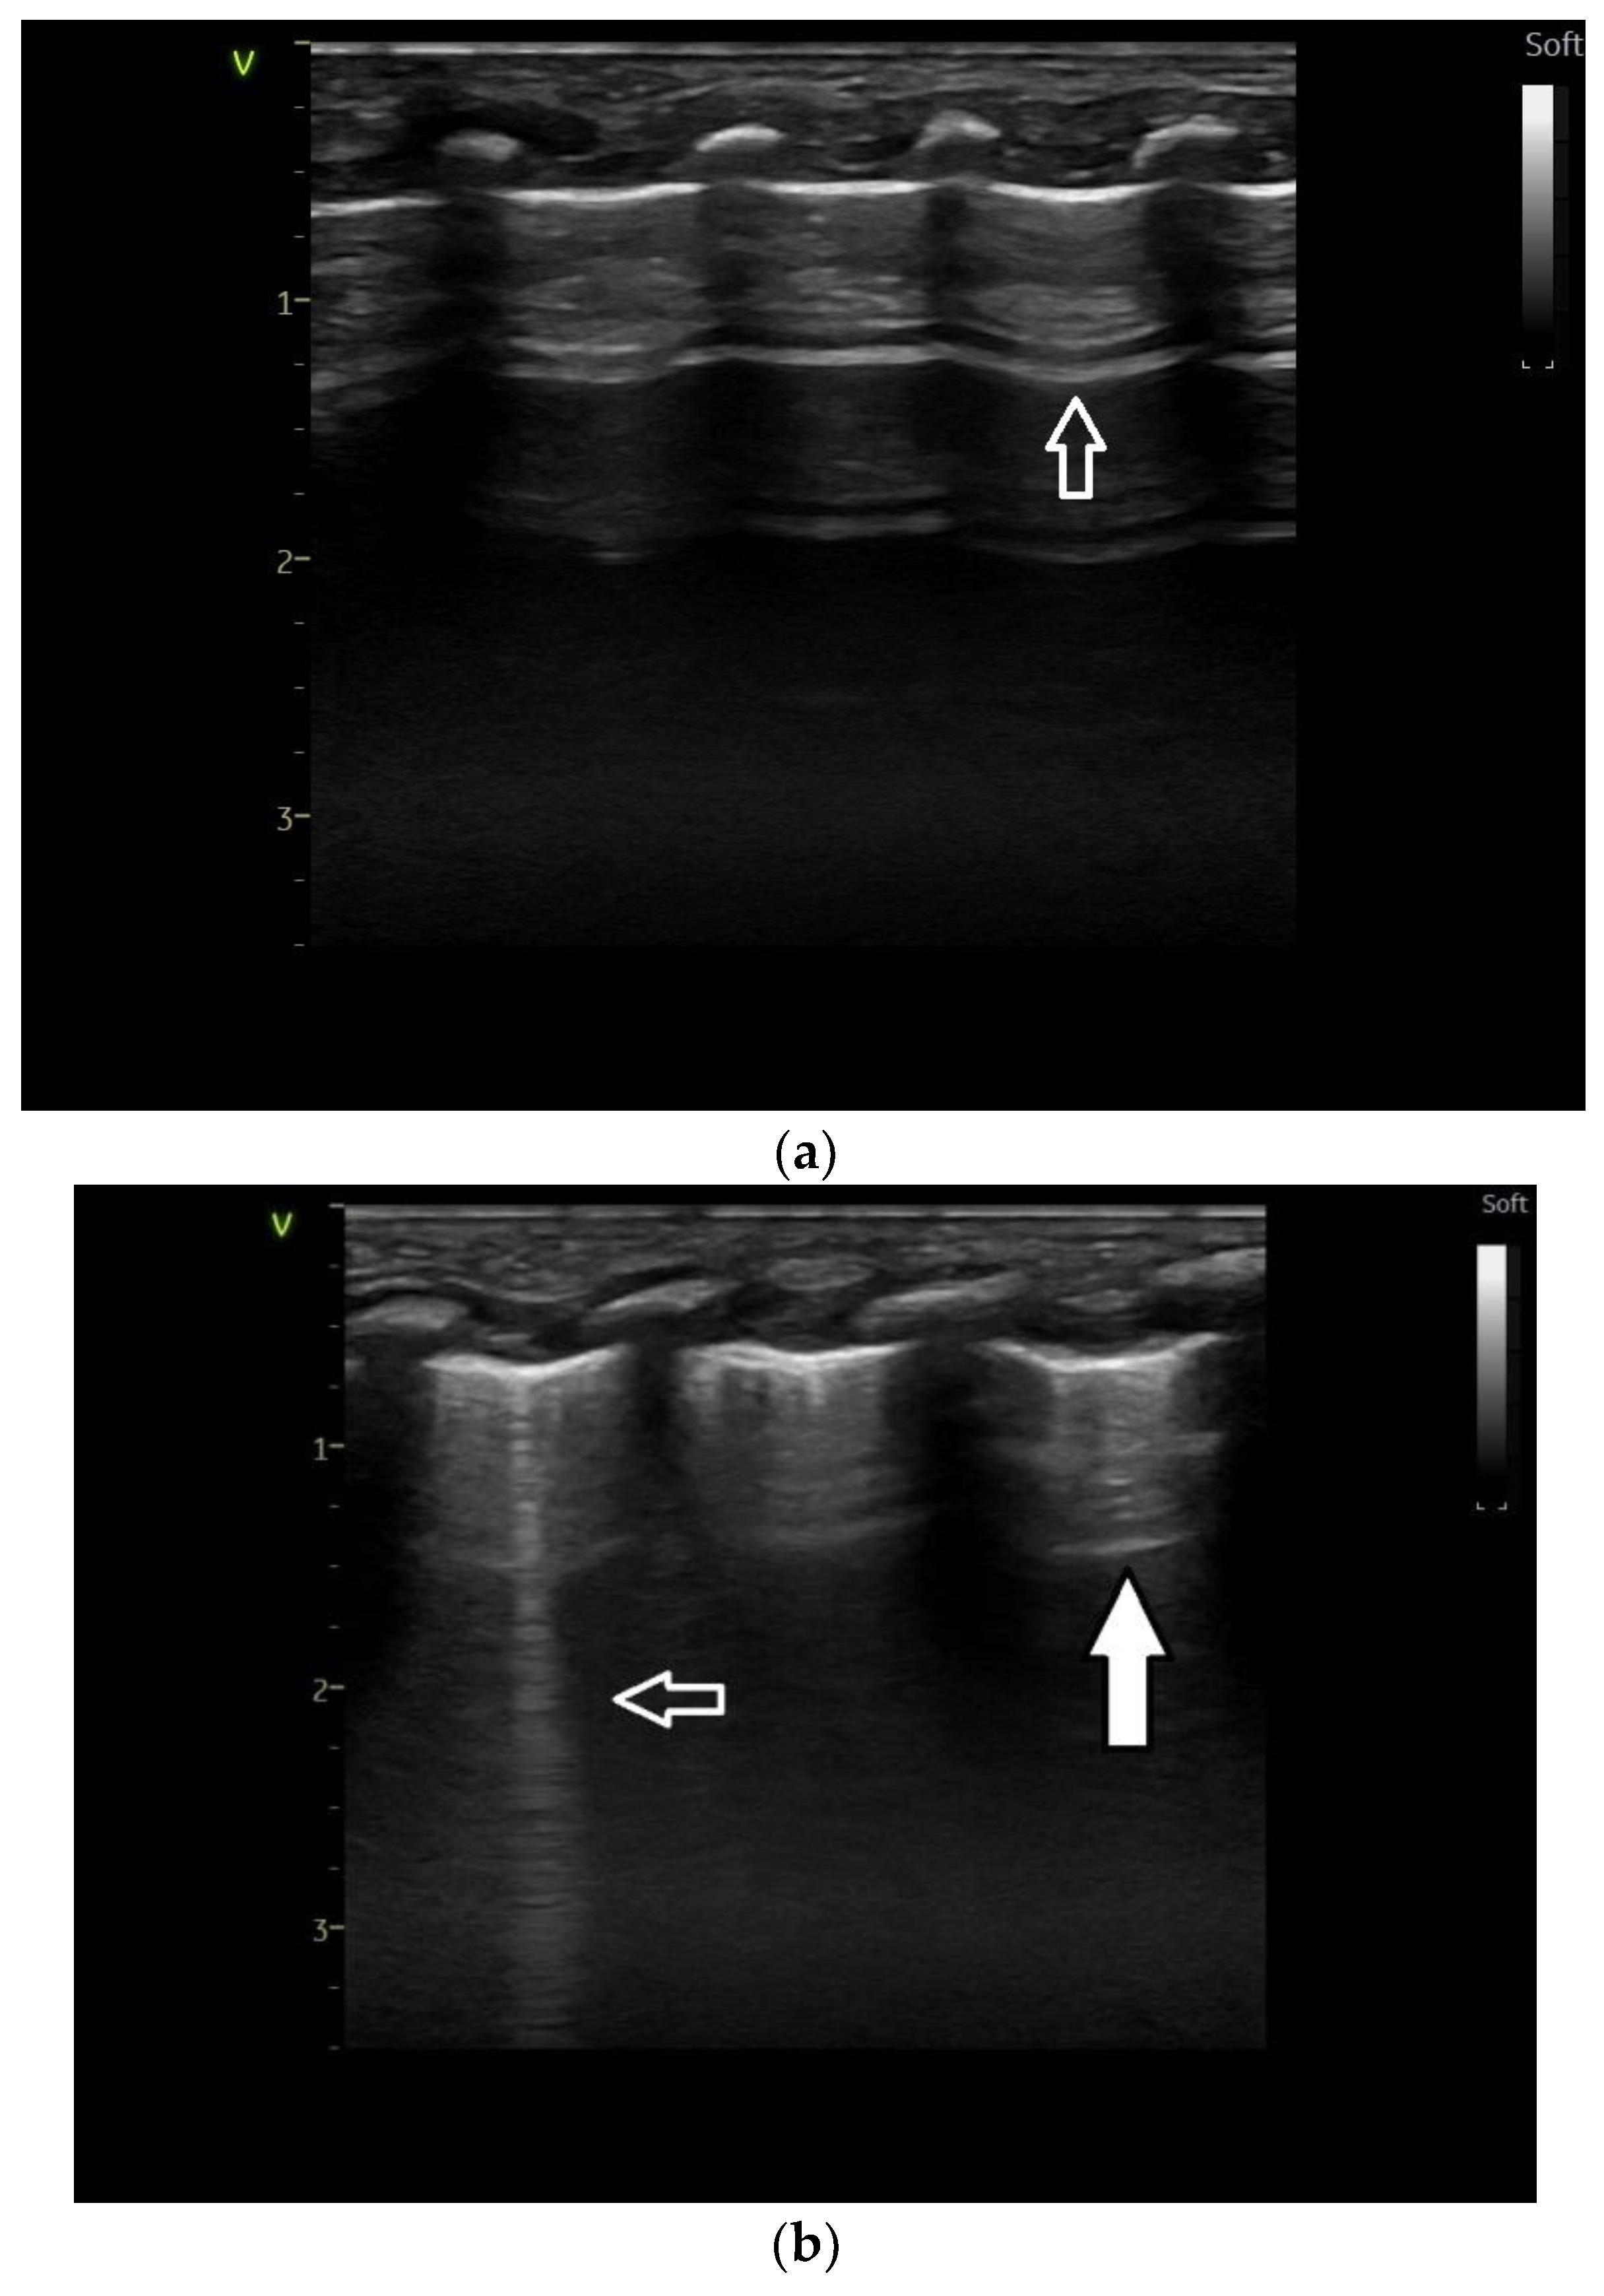

Lung ultrasound

2.3. Lung Ultrasound Criteria/Findings